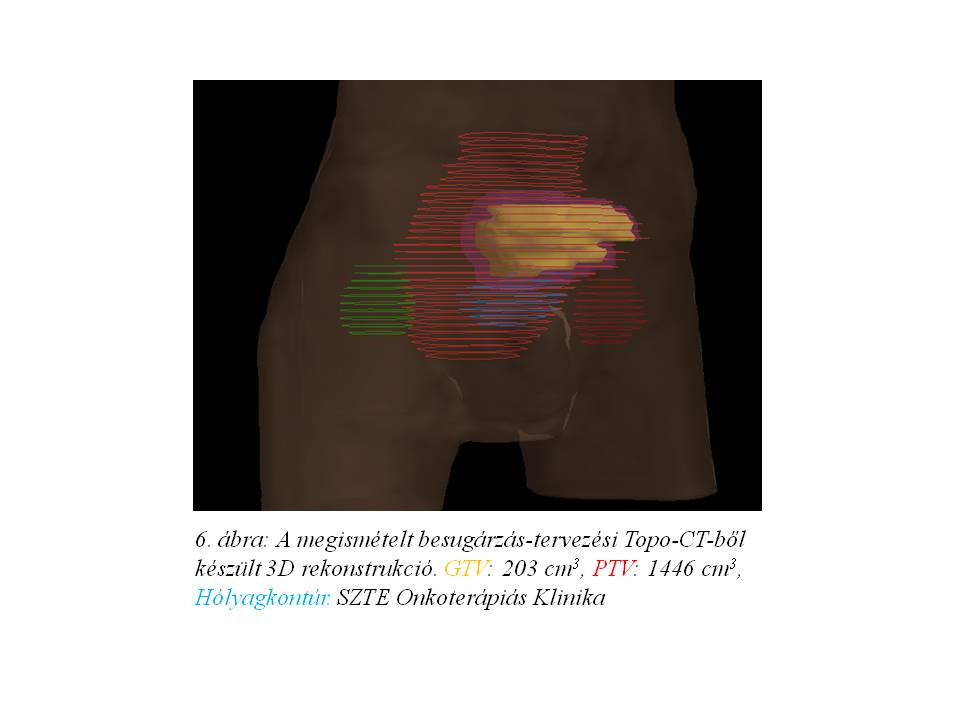

Opust követően az aktív onkológiai kezelés 2014 júliusában indult újra. A megismételt besugárzás-tervezési topo-CT (5. ábra, 6. ábra) mérsékelt tumoros regressziót igazolt. A beteg sugárkezelését további 17x1,8 Gy + a residualis makroszkópos tumornak megfelelően szűkített célterületre további 5x1,8 Gy összdózissal komplettáltuk, az 1. és 5. héten iv. 5FU+Leucovorin kemoterápiával kombinálva, tekintettel a korábbi compliance problémákra.